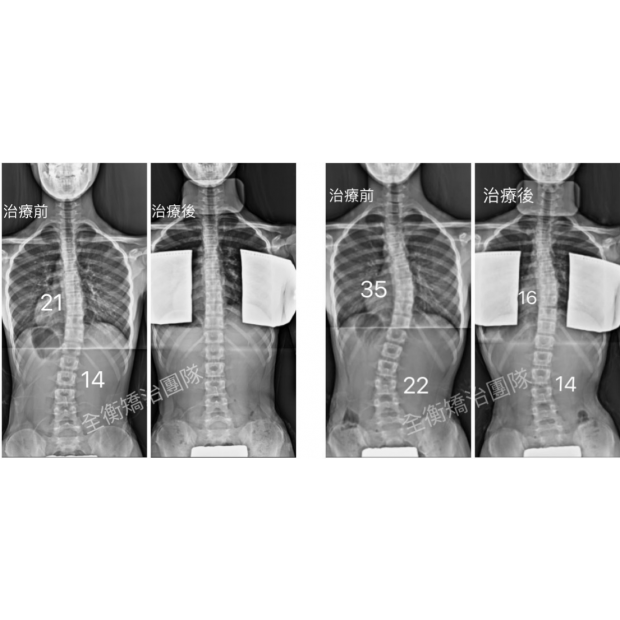

12嵗側彎女生,4個月,大C變小C12嵗側彎女生,4個月,大C變小C

這位12歲妹妹,小五時發現胸彎15度

來我們診所初診時已經惡化至35度

並伴隨15度的旋轉,背部右側隆起明顯

透過「德國施羅斯療法」的運動治療和背架矯正

4個月時間減少了16度,從大胸彎變成小胸彎 -